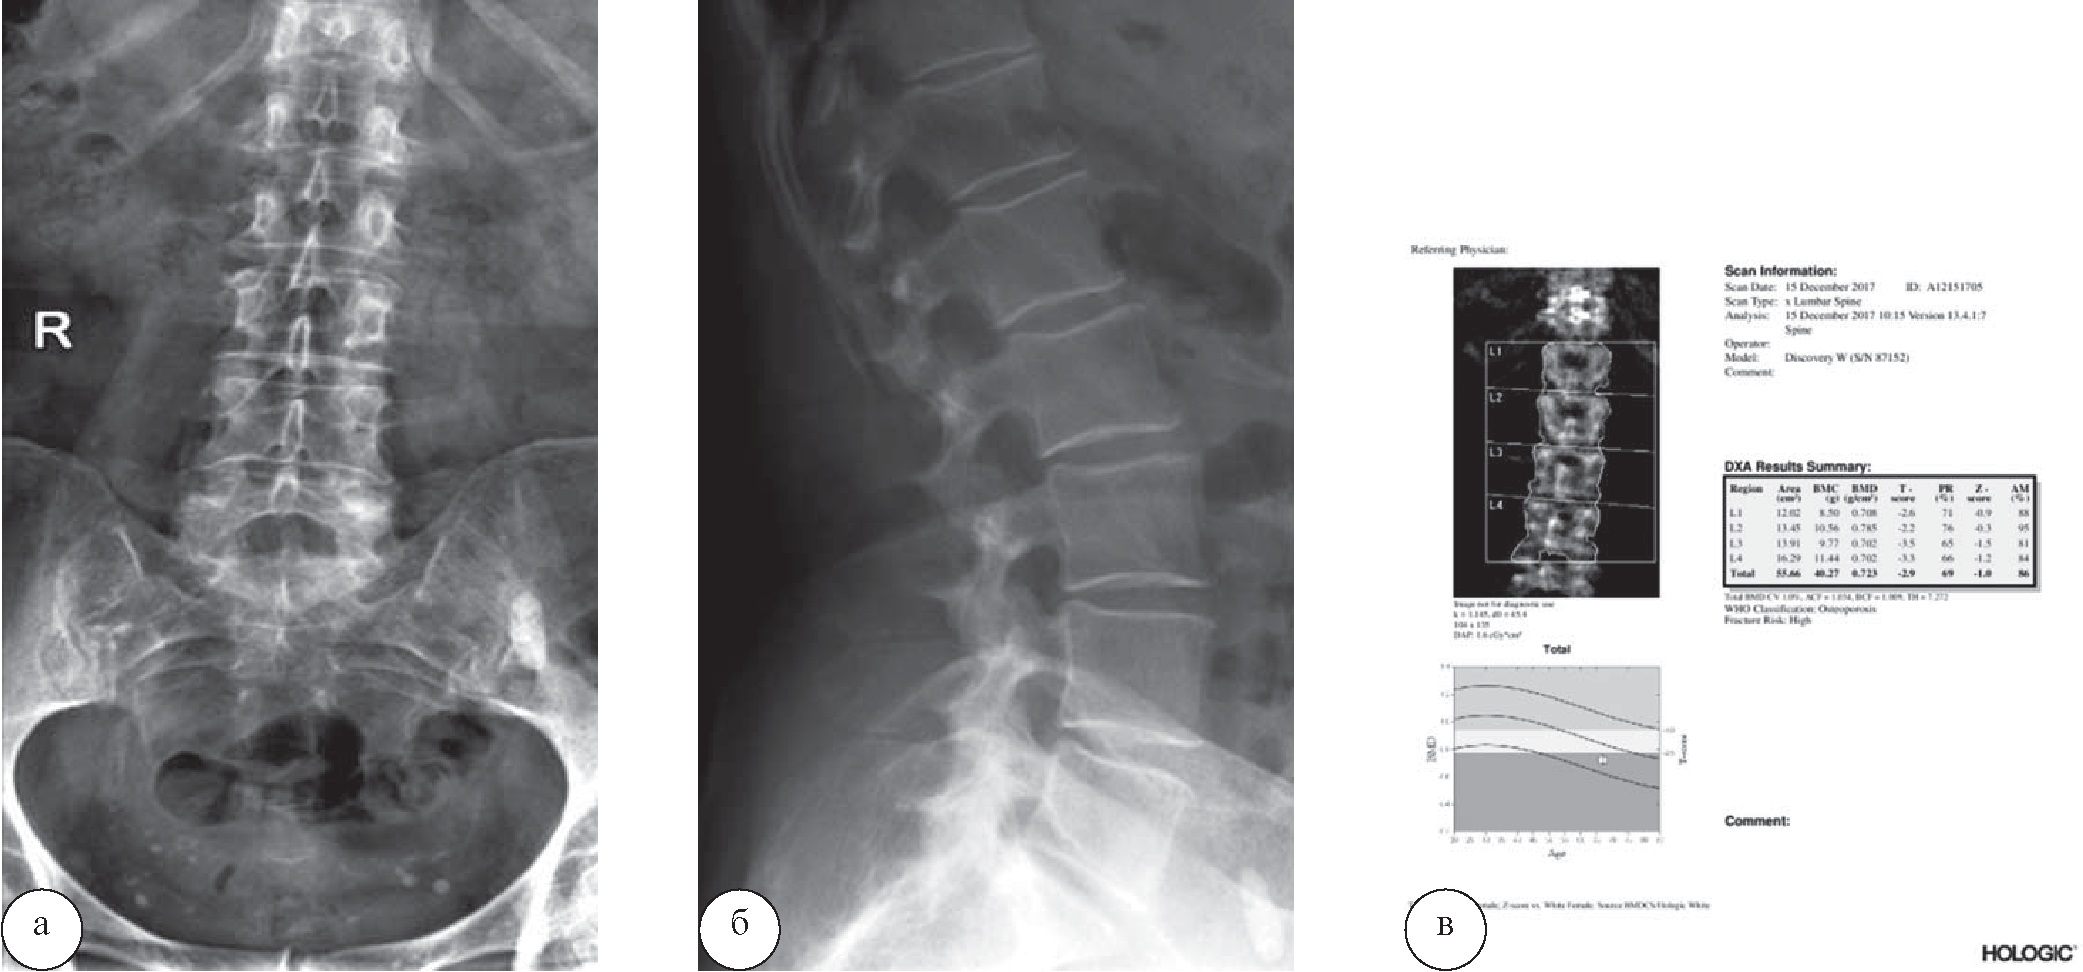

Случай выявления остеопороза при остеоденситометрии, выполненной в санатории, у пациентки 56 лет, прибывшей на лечение по поводу остеохондроза пояснично-крестцового отдела позвоночника, представлен на рисунке 2. В санаторной карте имелись лишь данные рентгенологического обследования, а у пациентки при себе – данные МРТ, подтверждающие диагноз направления. Остеоденситометрия была назначена в связи со следующими обстоятельствами: возраст свыше 40 лет, в анамнезе – менопауза ~10 лет, кормление грудью 11 месяцев, планируемое включение в программу лечения механотерапевтических воздействий (рис. 2).

Рис. 2. Пациентка Т., 56 лет с проявлениями остеохондроза пояснично-крестцового отдела позвоночника. При рентенографии пояснично-крестцового отдела позвоночника в прямой и боковой проекциях (а, б) определяются умеренные проявления остеохондроза поясничного отдела позвоночника. При выполнении остеоденситометрии (в) площадь сканируемой поверхности (Area) – 55,66 см2. Содержание костного минерала (BMC) – 40,27 г, проекционная минеральная плотность костной ткани (BMD) – 0,723 г/см2, Т-критерий= –2,9, Z-критерий = –1, минерализация костей поясничного отдела позвоночника – в пределах значений остеопороза

По итогам комплексного анализа полученных результатов и данных санаторной карты пациентке из программы лечения были исключены планируемые тракционная и мануальная терапия, а также душ Шарко; назначены лечебная гимнастика в бассейне, кинезитерапия на аппарате «Экзарта» и «Kinesis Omega», иглорефлексотерапия.